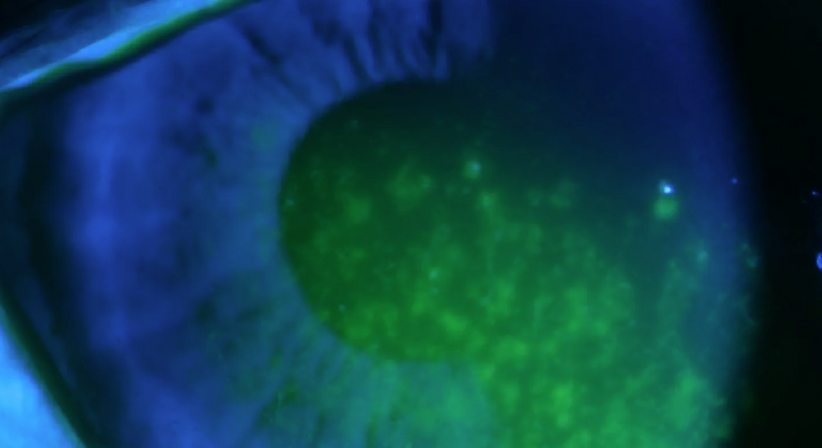

Mit dem Begriff „Trockenes Auge“ wird eine Benetzungsstörung der Augenoberfläche bezeichnet, die durch eine Verminderung der Tränenmenge (quantitative Tränenfilmstörung) oder durch eine veränderte Zusammensetzung der Tränenflüssigkeit (qualitative Tränenfilmstörung) hervorgerufen wird. Häufige Gründe können beispielsweise Klimaanlagen gepaart mit langer PC-Arbeit („Office-Eye Syndrom“) oder auch Medikamente (Antidepressiva) und hormonelle Umstellungen (Menopause) sein.